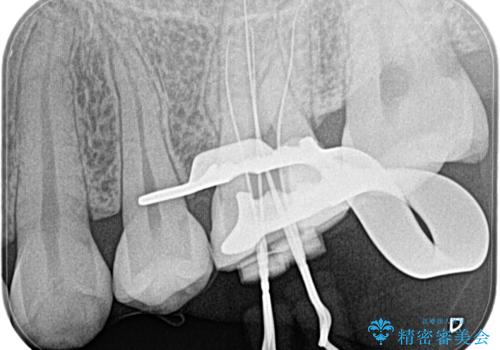

- 奥歯がズキズキ痛いことを主訴に来院されました。

検査の結果、診断を症候性不可逆性歯髄炎、症候性根尖性歯周炎とし抜髄を行っております。

主訴である痛みを解決することができました。無菌的治療を行うことで、根尖性歯周炎の予防にも期待できる治療を行いました。